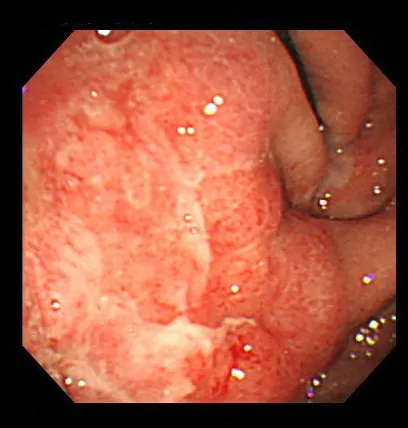

上部消化管内視鏡検査で残胃に腫瘍があり、生検で印環細胞癌と診断されました。